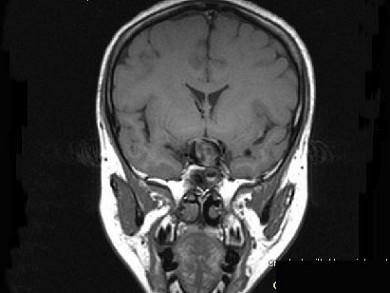

女,43岁,反复头痛10个月,CT检查如图,最可能诊断为 ( )A、脑膜瘤B、胶质瘤C、垂体瘤D、颈内动脉瘤E、颅咽管瘤

问题 女,43岁,反复头痛10个月,CT检查如图,最可能诊断为 ( )

选项 A、脑膜瘤 B、胶质瘤 C、垂体瘤 D、颈内动脉瘤 E、颅咽管瘤

答案 D